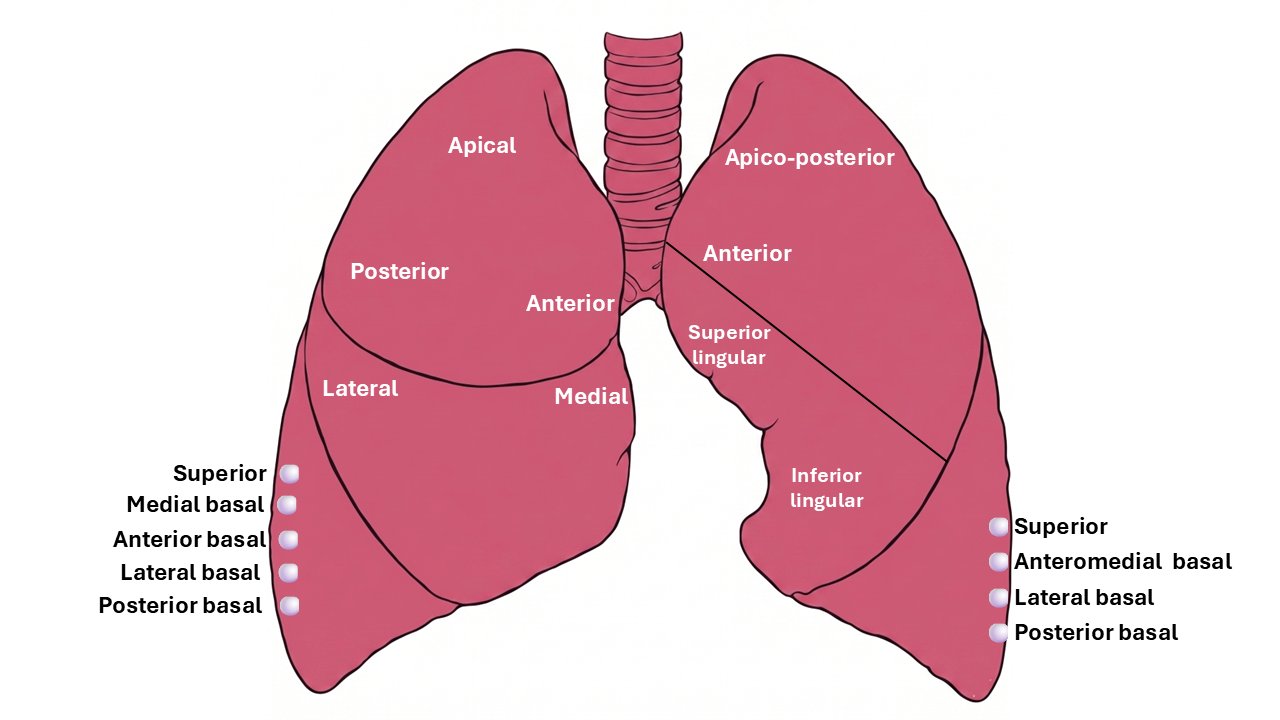

Bronchopulmonary segments

A bronchopulmonary segment (BPS) is an anatomical unit of lung supplied by a specific tertiary (segmental) bronchus with an accompanying segmental artery. The general pattern is 10 segments on the right and 8 segments on the left - LB1/2 and LB7/8 are typically fused on the left.

Pyramidal in shape - apex towards the root of the lung, base towards the surface. Each segment has its own arterial supply and segmental bronchus. Pulmonary veins run in intersegmental planes, not alongside bronchi - forming the surgical plane between adjacent segments.

Each BPS has no communication with adjacent segments - making segmentectomy possible without damaging neighbours. Intersegmental planes are marked by intersegmental veins, which serve as the surgical guide. There is little bleeding or air leak after segmentectomy if the intersegmental plane is correctly developed.